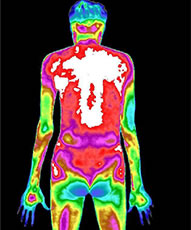

治疗前后炎症对比图/ Inflammation contrast

• 治疗前

• 治疗后